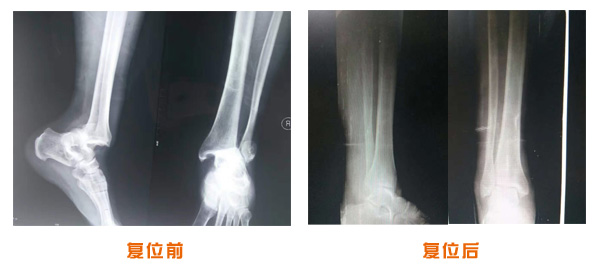

肘關節脫位骨折治療前后對比